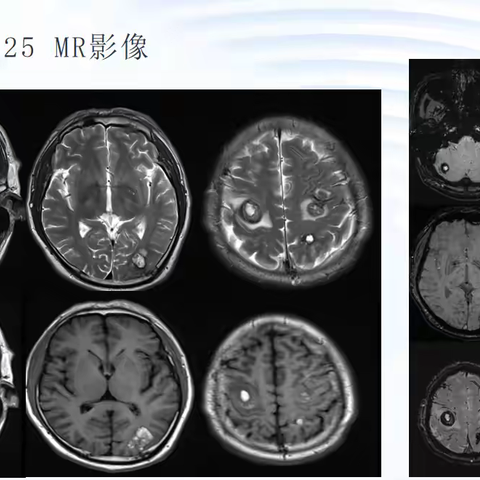

易被误认为脑转移瘤的病灶-多发胶质母细胞瘤